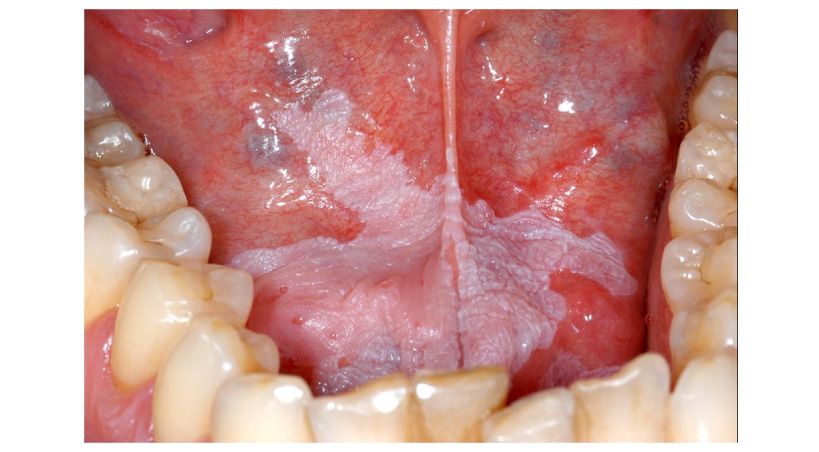

La sensibilidad dental se produce por la exposición de la dentina

La sensibilidad dental se produce por la exposición gradual de la parte más blanda del diente que se encuentra debajo del esmalte, denominada "dentina".